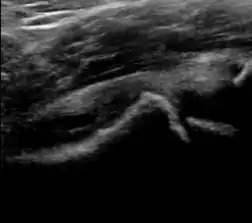

During childhood, ultrasound is a quick method to assess hip pain and quite often may be used to avoid use of irradiating techniques, such as radiography or CT. Ultrasound allows evaluation of joint effusion, synovial thickening and neovascularity, the bone/cartilage contour, and the femoral head-neck alignment. Although sonography is extremely sensitive in detecting increased synovial fluid, it is nonspecific and cannot be used with accuracy to determine the type of fluid. Transient synovitis of the hip, despite being the most frequent cause of pain in children between 3 and 10 years, remains a diagnosis of exclusion. It usually shows anechoic fluid, but echogenic fluid can also be found. The effusion is considered pathologic when it is measured at >2 mm in thickness. The differential diagnosis is wide, including osteomyelitis, septic arthritis, primary or metastatic lesions, LCPD, and SCFE. Discrimination from septic arthritis is challenging, often requiring joint aspiration. In septic arthritis, US is able to demonstrate a hip joint effusion, synovial thickening, and cartilage damage, although the appearances are nonspecific.[1]

A step between the head and the physis can be detected in children with SCFE, while abnormalities in the femoral head contour may suggest the presence of LCPD. In both cases, radiographs are mandatory to confirm diagnosis and severity (Figure 12).[1]

Figure 12: